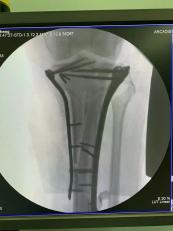

①髓内钉

胫骨干、股骨干、肱骨干等部位的骨折有时会使用髓内钉固定技术,由于髓内钉在骨内影响较小,因此可取可不取。